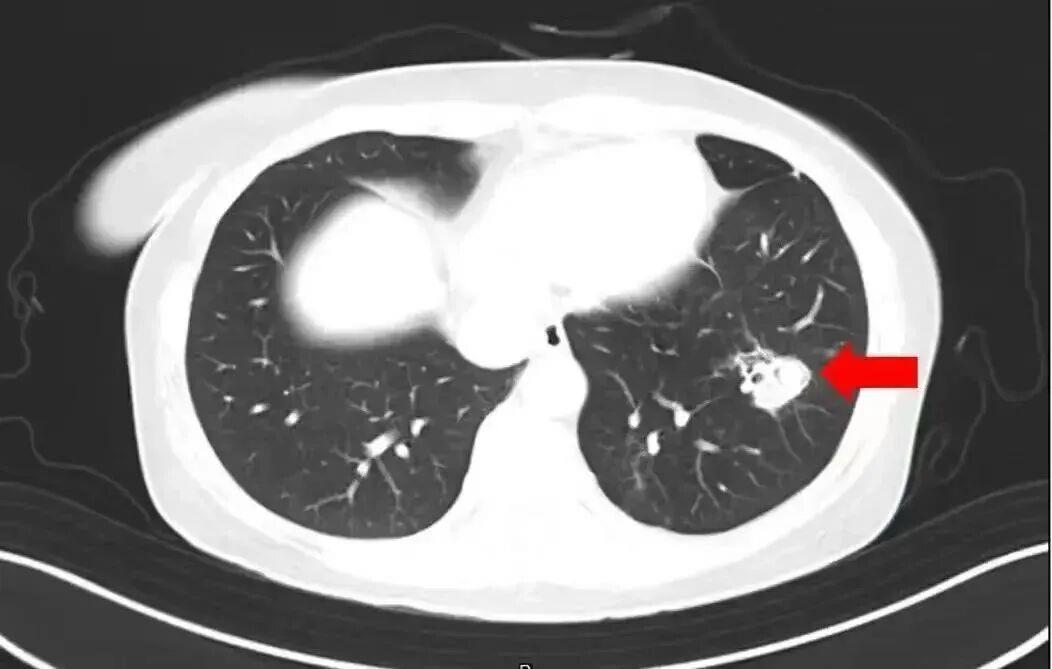

2025年1月,江苏扬州的张大爷为迎接春节开始大扫除,清扫过程中不慎吸入大量灰尘和霉菌孢子,导致哮喘发作。张大爷随即服用了常备的哮喘治疗药物,可症状反而逐渐加重。经检查,张大爷的肺部出现感染,确诊为肺曲霉病。

北京佑安医院感染综合科主任医师李侗曾介绍,对于免疫力低下的人,吸入了这些真菌,就会发病引起肺部的病变——曲霉肺炎。因为它是通过呼吸道感染的,进入血液后是可以扩散到全身。大脑因为血供最丰富,所以也是真菌最容易侵犯的器官。